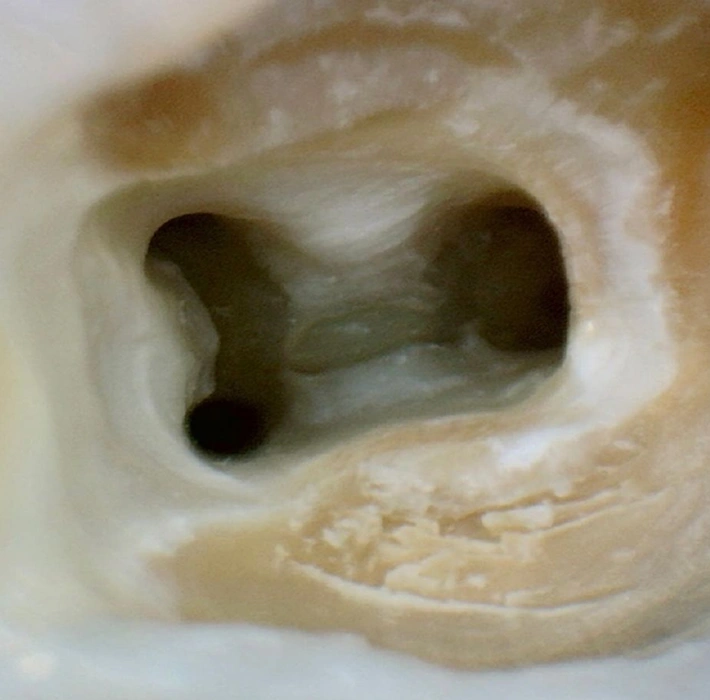

Tratamento Endodôntico (Canal)